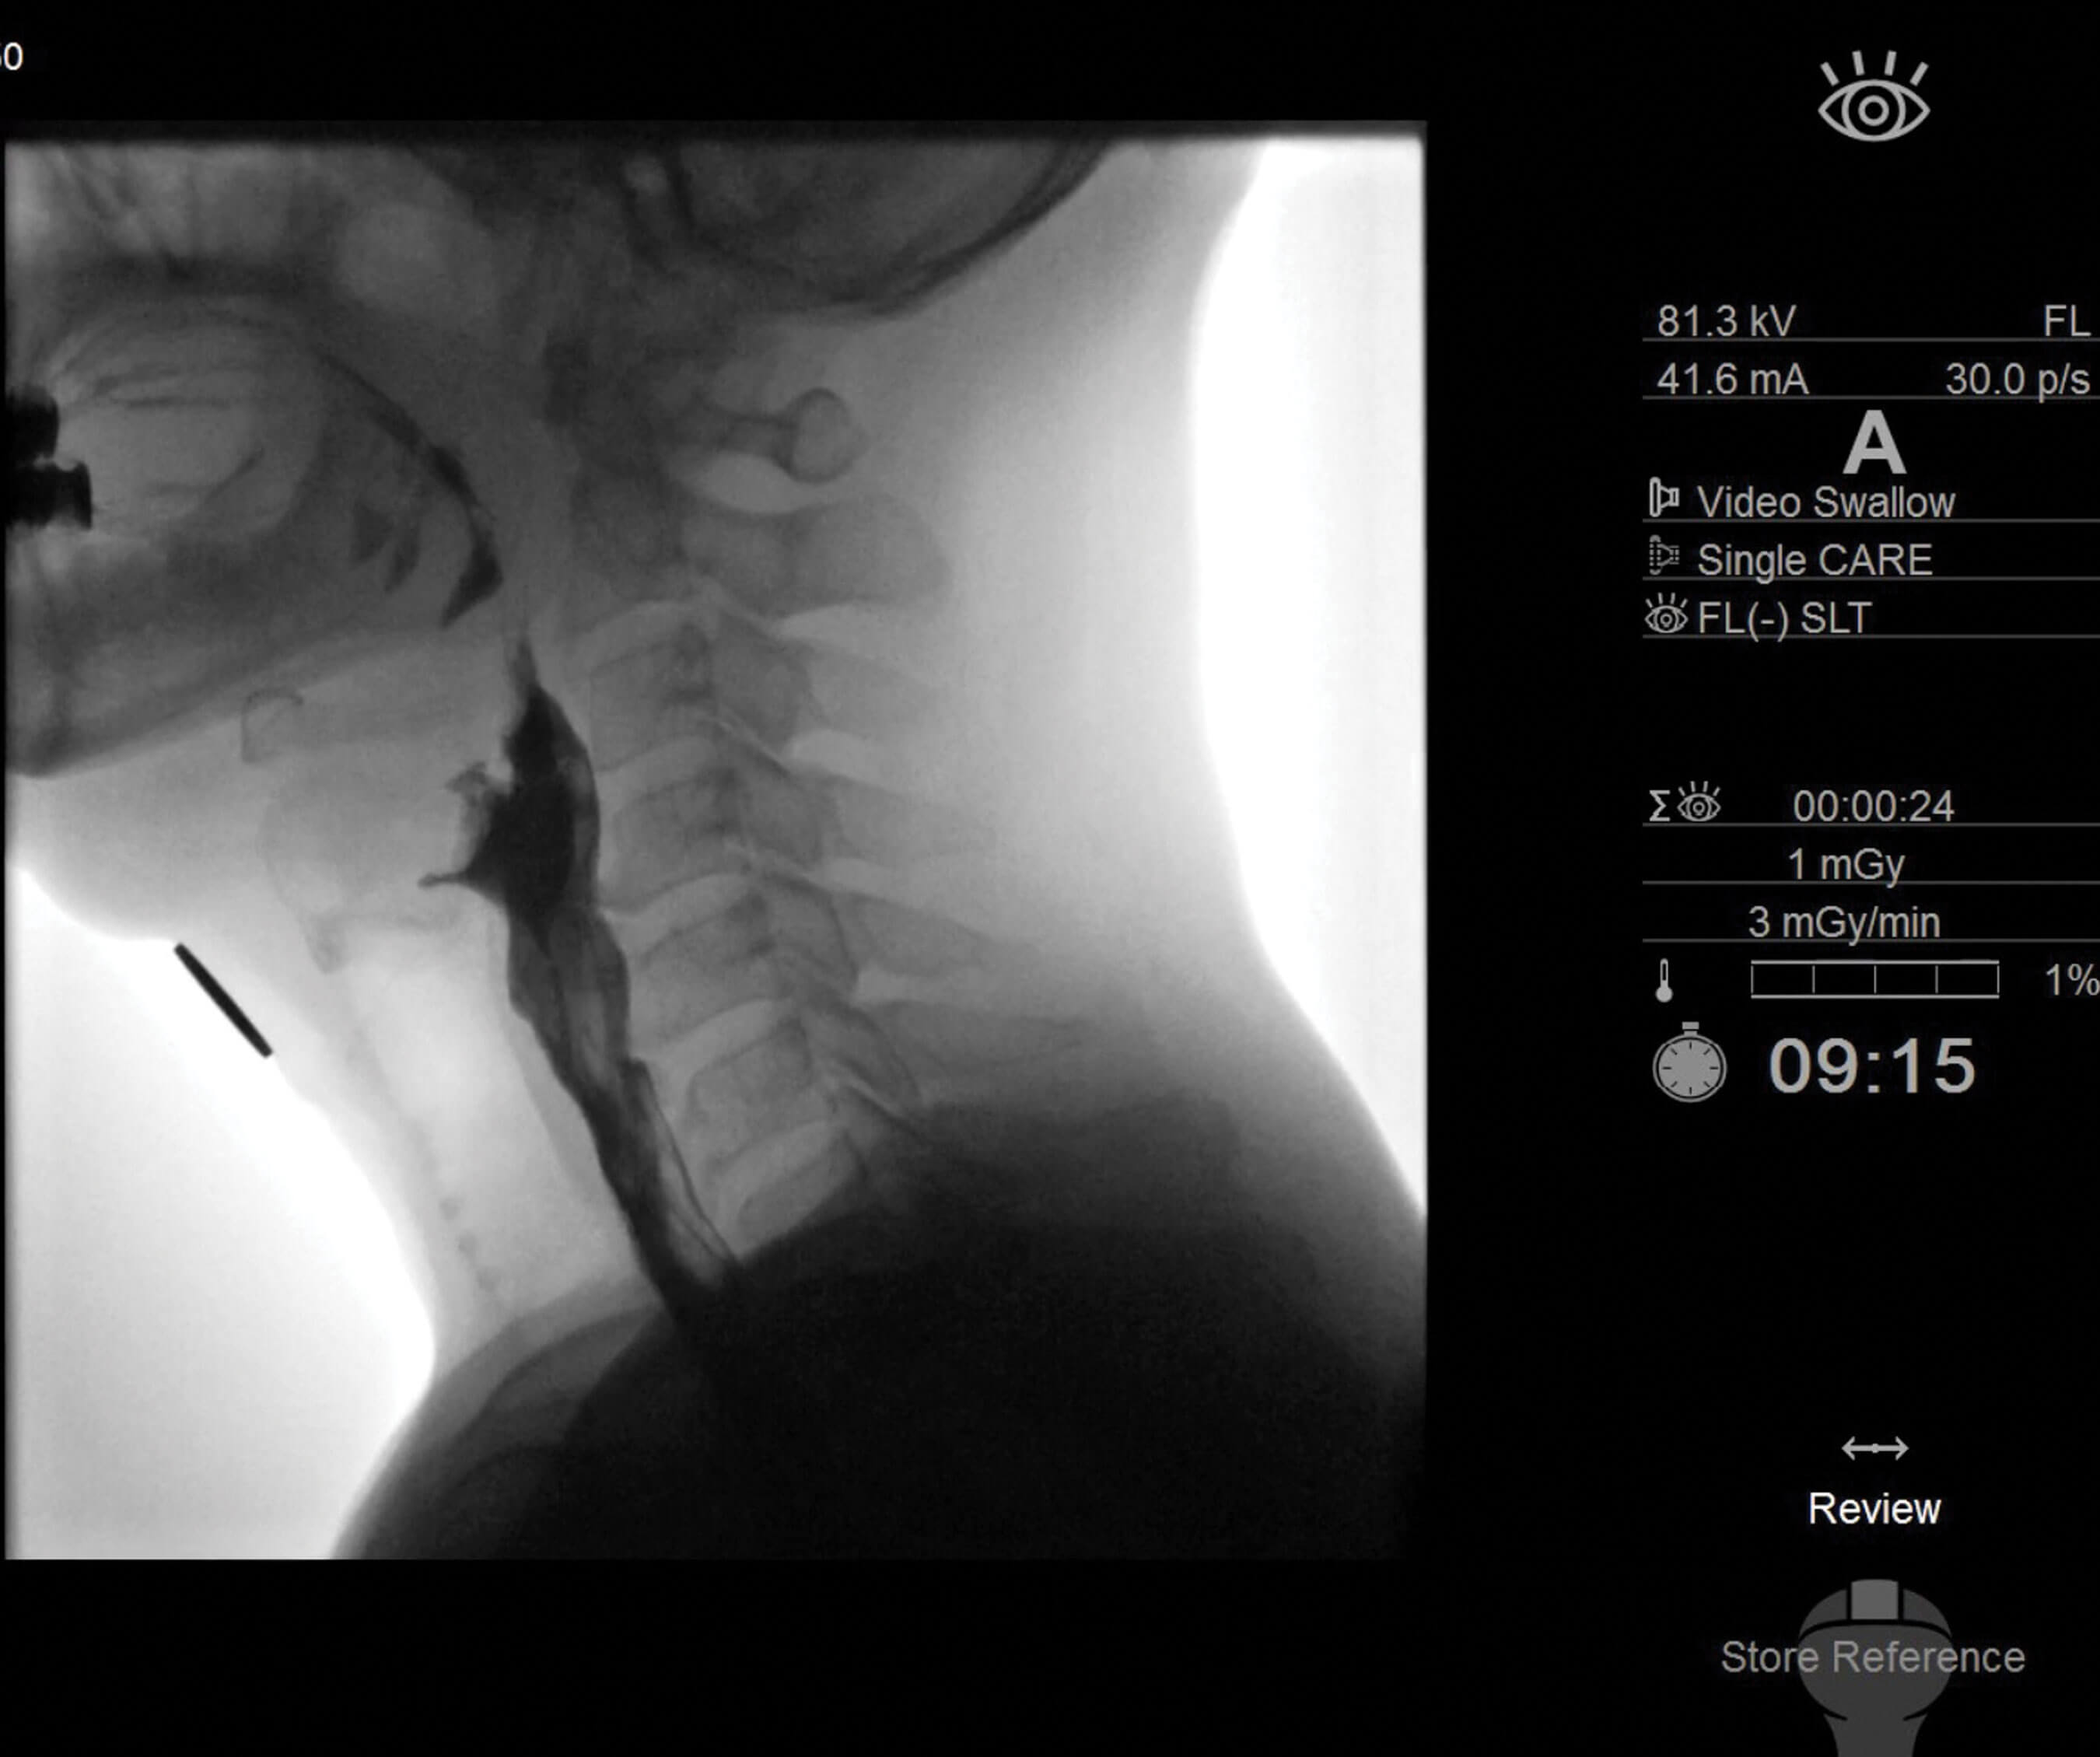

Figure 1. Lateral image during fluoroscopic swallowing study, mid swallow, centred on the pharynx

demonstrating anterior vertebral lipping of C4 and C5 indenting the barium stream.

Our understanding of the biomechanics of deglutition influences our proposed therapy strategies. Surgical interventions for swallowing problems are limited and the need for novel treatments in this area, particularly related to the pharynx, is acute. Our clinical laboratory at the University of Auckland explores deglutitive physiology across the age spectrum from newborns to centurions. We have developed an objective and quantitative approach to analysing swallowing, incorporating videofluoroscopic (Figure 1), manometric and cough-reflex data. A picture of the individual’s physiologic impairment is produced and from this we design interventions, treatment plans and pathways for re-assessment.